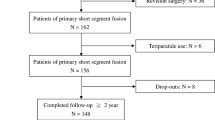

A total of 47 consecutive patients underwent laminectomy decompression, and multi-level instrumented posterolateral fusions were reviewed. Group 1 comprised 26 patients having DBM with autologous laminectomy bone (ALB). Group 2 consisted of 21 patients having AIBG with ALB. The fusion success evaluation was based on findings using the 12-month anteroposterior and dynamic plain radiographs.

After obtaining approval from the Institutional Review Board (IRB) of Chang Gung Medical Foundation (reference number: 103-5000B) without the need for informed consent due to retrospective study, 47 consecutive adult patients (11 males and 36 females), who underwent decompression and multi-level pedicle screw instrumented posterolateral fusion (≧ three-level fusion) between January 2009 and December 2013 were retrospective reviewed. The mean patient age was 66.3 ± 8.3 years old (range: 52–87 years old). Medical charts were reviewed, including diagnosis, surgical procedures, and postoperative complications. All the cases were diagnosed and treated based on clinical symptoms, plain radiographs, and magnetic resonance imaging studies. After the failure of initial conservative treatments, surgery was performed as a treatment option. The indications for surgery included lumbar spinal stenosis with spondylolisthesis and scoliosis (n = 41) and failed earlier back surgery (n = 6). All the patients underwent laminectomy for nerve decompression with pedicle screw instrumentation and posterolateral fusion including three-level instrumentation and fusion in 24 patients, four-level instrumentation and fusion in 20 patients, five-level instrumentation and fusion in 1 patient, six-level instrumentation and fusion in 1 patient, and seven-level instrumentation and fusion in 1 patient. The patients were divided into two groups. Group 1 comprised 26 consecutively operated patients (6 males and 20 females with a mean age of 67.2 ± 9.4 years) in whom DBM was used. Group 2 (control group) consisted of 21 consecutively operated patients (5 males and 16 females with a mean age of 65.1 ± 6.7 years) operated on prior to the introduction of DBM in our department. Autologous iliac bone graft was used for group 2 patients. Twelve patients in group 1 and eight patients in group 2 underwent posterior lumbar interbody fusion (PLIF) or transforaminal lumbar interbody fusion (TLIF) for sagittal and coronal alignment correction. Gender, age, TLIF/PLIF procedures, and the number of fusion levels were similar for both groups (Table 1).